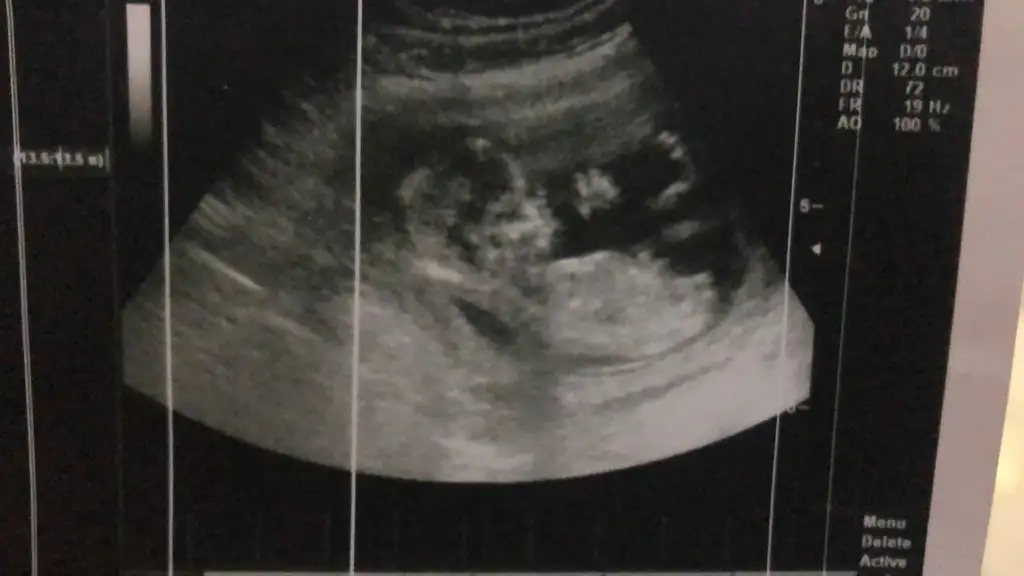

Karın ultrasonu, tahmin yapabilir misiniz ☺️

6+6 haftalık karından ultrason bana da yorum yapabilir misiniz?